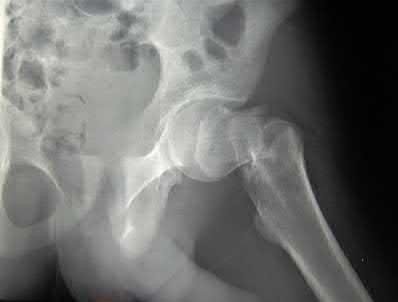

A 35 year-old female presents after prolonged extrication from a motor vehicle collision complaining of severe pelvic pain. Physical examination reveals diminished perianal sensation. She is otherwise neurologically intact. Figures A through D are radiographs and representative CT cuts of her injury. Which of the following nerve roots has likely been injured by the acute trauma?

The clinical scenario is consistent with a high-energy sacral fracture. The radiographs in figures A and B demonstrate a sacral fracture with posterior displacement of the right hemipelvis seen on the inlet view. Figures C and D are axial and sagittal CT images which show a displaced fracture of the right

hemisacrum along with a transvere fracture component through the S3 body . Diminished perianal sensation is concerning for an S2 nerve root injury.

Mehta et al reviewed the current management of sacral fractures. They note that the S1 and S2 nerve roots are more likely to be injured with sacral fractures as they occupy 1/3 to 1/4 of the neural foramina, as opposed to S3 and S4, which only occupy 1/6 of the neural foramina.

Robles reviewed the current literature to ascertain principles of evaluation and treatment for transverse sacral fractures. The author notes that injury to nerve roots S2 to S5 is manifested by impairment of urinary and anal continence and sexual function.